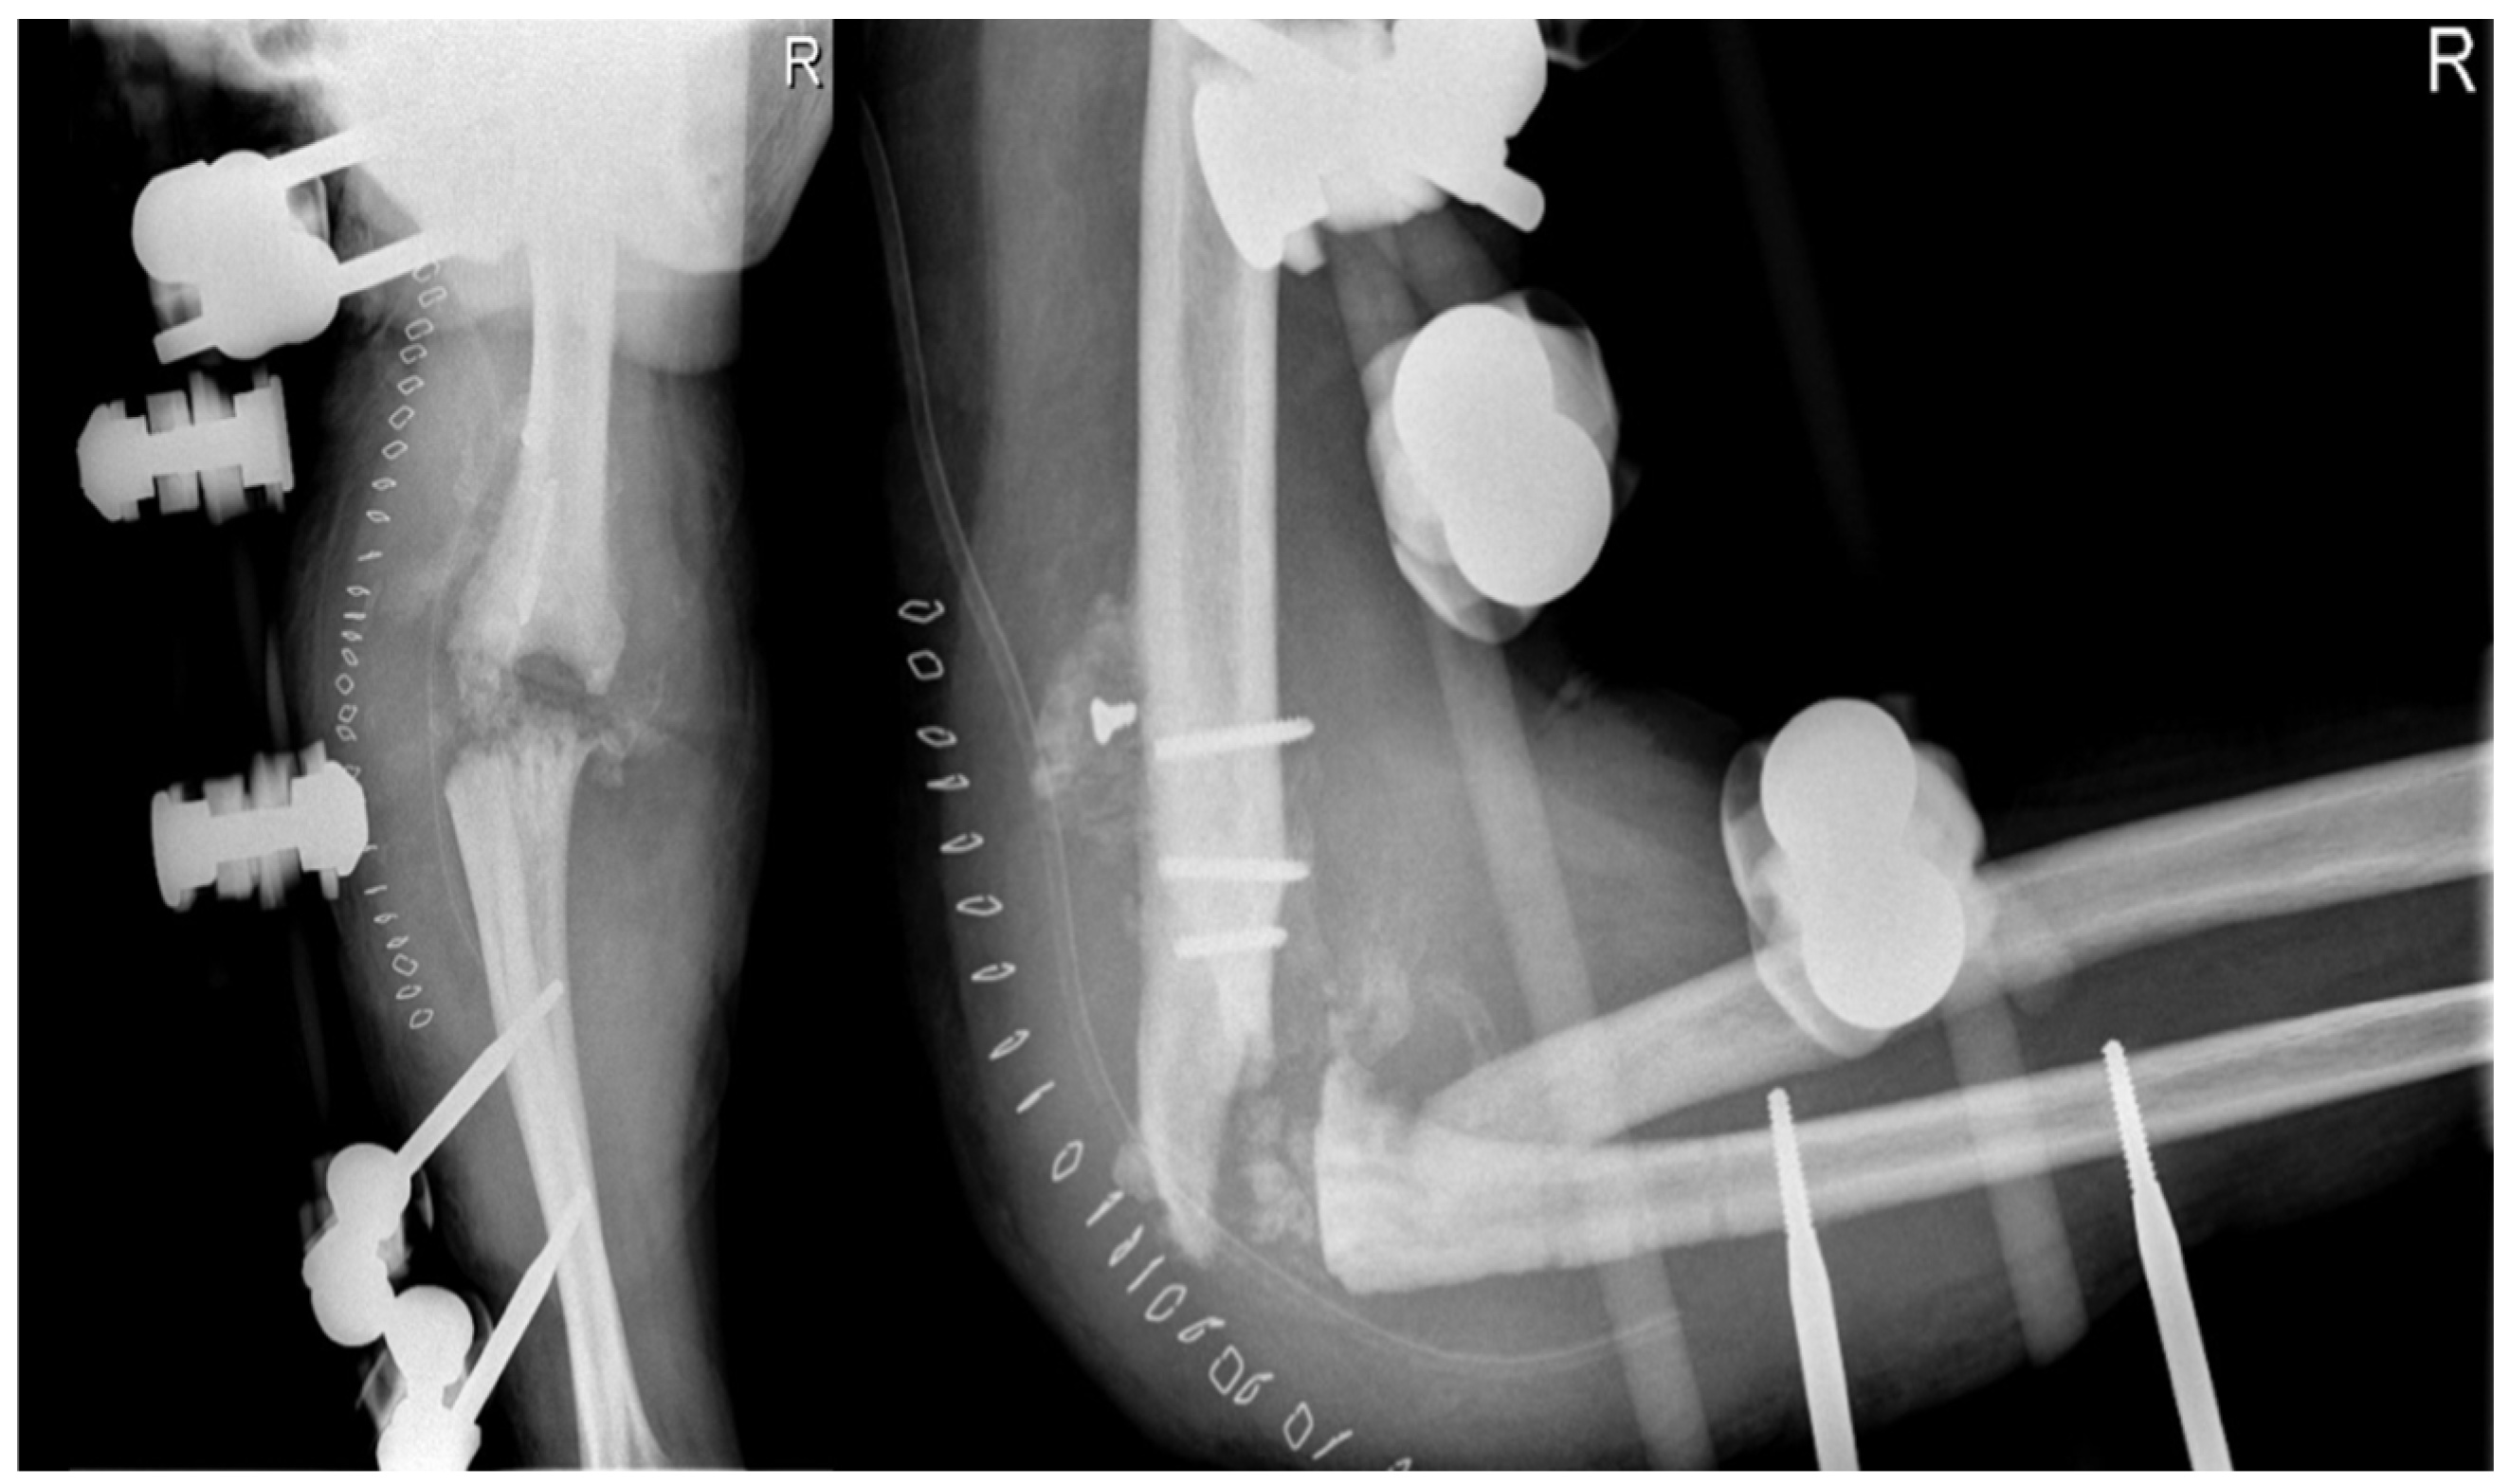

2. Case Presentation

2.4.4. Arthrodesis

- Evidence from the Scientific Literature

Arthrodesis and Complications

2.4.6. Revision Total Elbow Arthroplasty